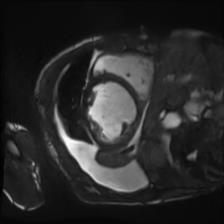

Recently, deep neural networks have greatly advanced undersampled Magnetic Resonance Image (MRI) reconstruction, wherein most studies follow the one-anatomy-one-network fashion, i.e., each expert network is trained and evaluated for a specific anatomy. Apart from inefficiency in training multiple independent models, such convention ignores the shared de-aliasing knowledge across various anatomies which can benefit each other. To explore the shared knowledge, one naive way is to combine all the data from various anatomies to train an all-round network. Unfortunately, despite the existence of the shared de-aliasing knowledge, we reveal that the exclusive knowledge across different anatomies can deteriorate specific reconstruction targets, yielding overall performance degradation. Observing this, in this study, we present a novel deep MRI reconstruction framework with both anatomy-shared and anatomy-specific parameterized learners, aiming to "seek common ground while reserving differences" across different anatomies.Particularly, the primary anatomy-shared learners are exposed to different anatomies to model flourishing shared knowledge, while the efficient anatomy-specific learners are trained with their target anatomy for exclusive knowledge. Four different implementations of anatomy-specific learners are presented and explored on the top of our framework in two MRI reconstruction networks. Comprehensive experiments on brain, knee and cardiac MRI datasets demonstrate that three of these learners are able to enhance reconstruction performance via multiple anatomy collaborative learning.

翻译:最近,深心神经网络大大推进了未经充分取样的磁共振成像(MRI)重建,其中大多数研究都遵循单一解剖一个网络的方式,即每个专家网络都经过特定解剖学的培训和评价。除了在培训多种独立模型方面效率低下之外,这种公约忽视了不同解剖学中共享的、可相互受益的解析知识。为了探索共享知识,一种天真的方法是将各解剖学家的所有数据结合起来,以训练一个全方位网络。不幸的是,尽管存在共享的解析知识,但我们发现,不同解剖学的独家知识可以恶化具体的重建目标,导致总体性能退化。在这项研究中,我们提出了一个新型的深度解剖重建框架,既有解剖学共享知识,又具有具体的解剖学参数,目的是“寻找共同的土壤,同时保留不同解剖学家之间的差异。此外,主要的解剖学学习者将接触不同的解剖学数据,通过多种解剖学重建的模型,并用不同的解剖学研究者将数据展示出一个全方位基础。